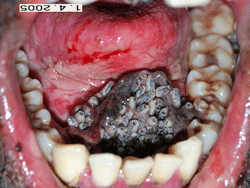

Paciente masculino de 40 años de edad, raza negra, indigente, con antecedentes de alcoholismo fue admitido en el Hospital Estadual "Getúlio Vargas" , Rio de Janeiro,Brasil, víctima de agresión física. Los exámenes de laboratorio que se le pratiicaron luego de ser admitido, refirieron solamente la presencia de anemia discreta (HCT= 35,1L%). Dos días después de ser hospitalizado se solicitó al Departamento de Cirugía Buco-Maxilo-Facial que dicho paciente fuese evaluado debido a la presencia de lesiones en cavida bucal. Al examen clínico se detectaron moscas sobre el paciente que se hallaba en estado semiinconsciente. Se observaron grandes masas de tejido necrótico con larvas en el paladar, así como en las zonas vestíbulo maxilar y mandibular, tabla bucal, y borda interna del ojo izquierdo. Se observó supuración en algunas áreas y olor fétido. La remoción de las larvas y tejido necrótico se realizó sin anestesia empleando para ello gasas, pinzas y se retiraron cerca de 300 larvas de color amarillo, con rayas negras longitudinales y de aproximadamente 10 milímetros de longitud, las cuales fueron depositadas en un envase con éter.Se inició el tratamiento con invermectina una vez al día a través de una sonda nasogástrica.El paciente en un período de 1 semana presentó escorias nitrogenadas (urea= 233mg/dl y creatina= 15,9mg/dl) y empeoramiento de la anemia (hct = 28.5 L%). Diez días después de ser hospitalizado, falleció a consecuencia de una insuficiencia respiratoria.

El paciente en cuestión presentó dos localizaciones raras del miasis: en cavidad ocular y en cavida bucal. Se confirma, de acuerdo con la literatura, que miasis en seres humanos es una afección que se encuentra más comúnmente en zonas tropicales y está relacionada con la pobreza y con pacientes débiles.El diagnostico de la miasis es clinico y, dependiendo del período de la evolución, Se puede observar inflamación, perforación y necrosis de los tejidos, olor fétido y movimiento de las larvas,. Estas características coinciden con las observaciones clínicas realizadas en nuestro caso. Sin embargo, en ausencia de este movimiento, además del examen visual clínico, la exploración quirúrgica y los hallazgos histopatológicos conllevan al diagnostico definitivo.(3) Las moscas pueden ser identificadas por medio de sus placas pigmentación de la tráquea y de las aberturas espiculares.(10) Algunos autores (10,11,12) hacen mención a la importancia del diagnostico precoz de Miasis, una vez que las larvas pueden infiltrarse, lo que causa la destrucción extensa de los tejidos y daños permanentes que provocan inclusive muerte al paciente